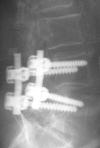

Delayed complications following lumbar spine fusion may occur amongst which is adjacent segment degeneration (ASD). Although interspinous implants have been successfully used in spinal stenosis to authors' knowledge such implants have not been previously used to reduce ASD in instrumented lumbar fusion. This prospective controlled study was designed to investigate if the implantation of an interspinous implant cephalad to short lumbar and lumbosacral instrumented fusion could eliminate the incidence of ASD and subsequently the related re-operation rate. Groups W and C enrolled initially each 25 consecutive selected patients. Group W included patients, who received the Wallis interspinous implant in the unfused vertebral segment cephalad to instrumentation and the group C selected age-, diagnosis-, level-, and instrumentation-matched to W group patients without interspinous implant (controls). The inclusion criterion for Wallis implantation was UCLA arthritic grade <II, while the exclusion criteria were previous lumbar surgery, severe osteoporosis or degeneration >UCLA grade II in the adjacent two segments cephalad to instrumentation. All patients suffered from symptomatic spinal stenosis and underwent decompression and 2-4 levels stabilization with rigid pedicle screw fixation and posterolateral fusion by a single surgeon. Lumbar lordosis, disc height (DH), segmental range of motion (ROM), and percent olisthesis in the adjacent two cephalad to instrumentation segments were measured preoperatively, and postoperatively until the final evaluation. VAS, SF-36, and Oswestry Disability Index (ODI) were used. One patient of group W developed pseudarthrosis: two patients of group C deep infection and one patient of group C ASD in the segment below instrumentation and were excluded from the final evaluation. Thus, 24 patients of group W and 21 in group C aged 65+ 13 and 64+ 11 years, respectively were included in the final analysis. The follow-up averaged 60 +/- 6 months. The instrumented levels averaged 2.5 + 1 vertebra for both groups. All 45 spines showed radiological fusion 8-12 months postoperatively. Lumbar lordosis did not change postoperatively. Postoperatively at the first cephalad adjacent segment: DH increased in the group W (P = 0.042); ROM significantly increased only in group C (ANOVA, P < 0.02); olisthesis decreased both in flexion (P = 0.0024) and extension (P = 0.012) in group W. The degeneration or deterioration of already existed ASD in the two cephalad segments was shown in 1 (4.1%) and 6 (28.6%) spines in W and C groups, respectively. Physical function (SF-36) and ODI improved postoperatively (P < 0.001), but in favour of the patients of group W (P < 0.05) at the final evaluation. Symptomatic ASD required surgical intervention was in 3 (14%) patients of group C and none in group W. ASD remains a significant problem and accounts for a big portion of revision surgery following instrumented lumbar fusion. In this series, the Wallis interspinous implant changed the natural history of ASD and saved the two cephalad adjacent unfused vertebra from fusion, while it lowered the radiographic ASD incidence until to 5 years postoperatively. Longer prospective randomized studies are necessary to prove the beneficial effect of the interspinous implant cephalad and caudal to instrumented fusion. We recommend Wallis device for UCLA degeneration I and II.